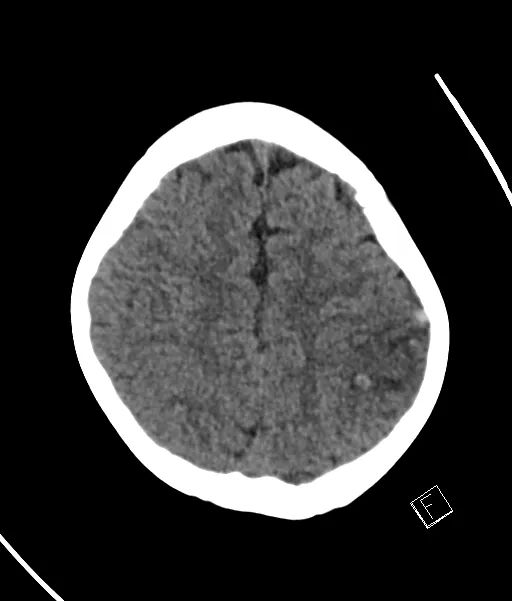

CASE F30 吞咽困难,构音障碍,右上肢感觉减退。产后5天。

有一个明显的高密度皮质静脉(致密静脉征),代表上吻合静脉,临近皮层增厚伴低密度,没有致密动脉征象。

左侧皮质浅静脉(Trolard)扩张和高密度,上矢状窦内有进一步的高密度病灶。

楔形低密度病灶可见于左上顶叶,伴有小病灶的实质出血。

左侧皮质浅静脉血栓形成,局部血栓延伸至上矢状窦,如下图,并伴有左上顶叶出血性静脉梗死。

上吻合静脉(Trolard静脉)是最大的一对浅表静脉,引流至上矢状窦。

在这个病例中,未增强的CT很好地显示了高密度。